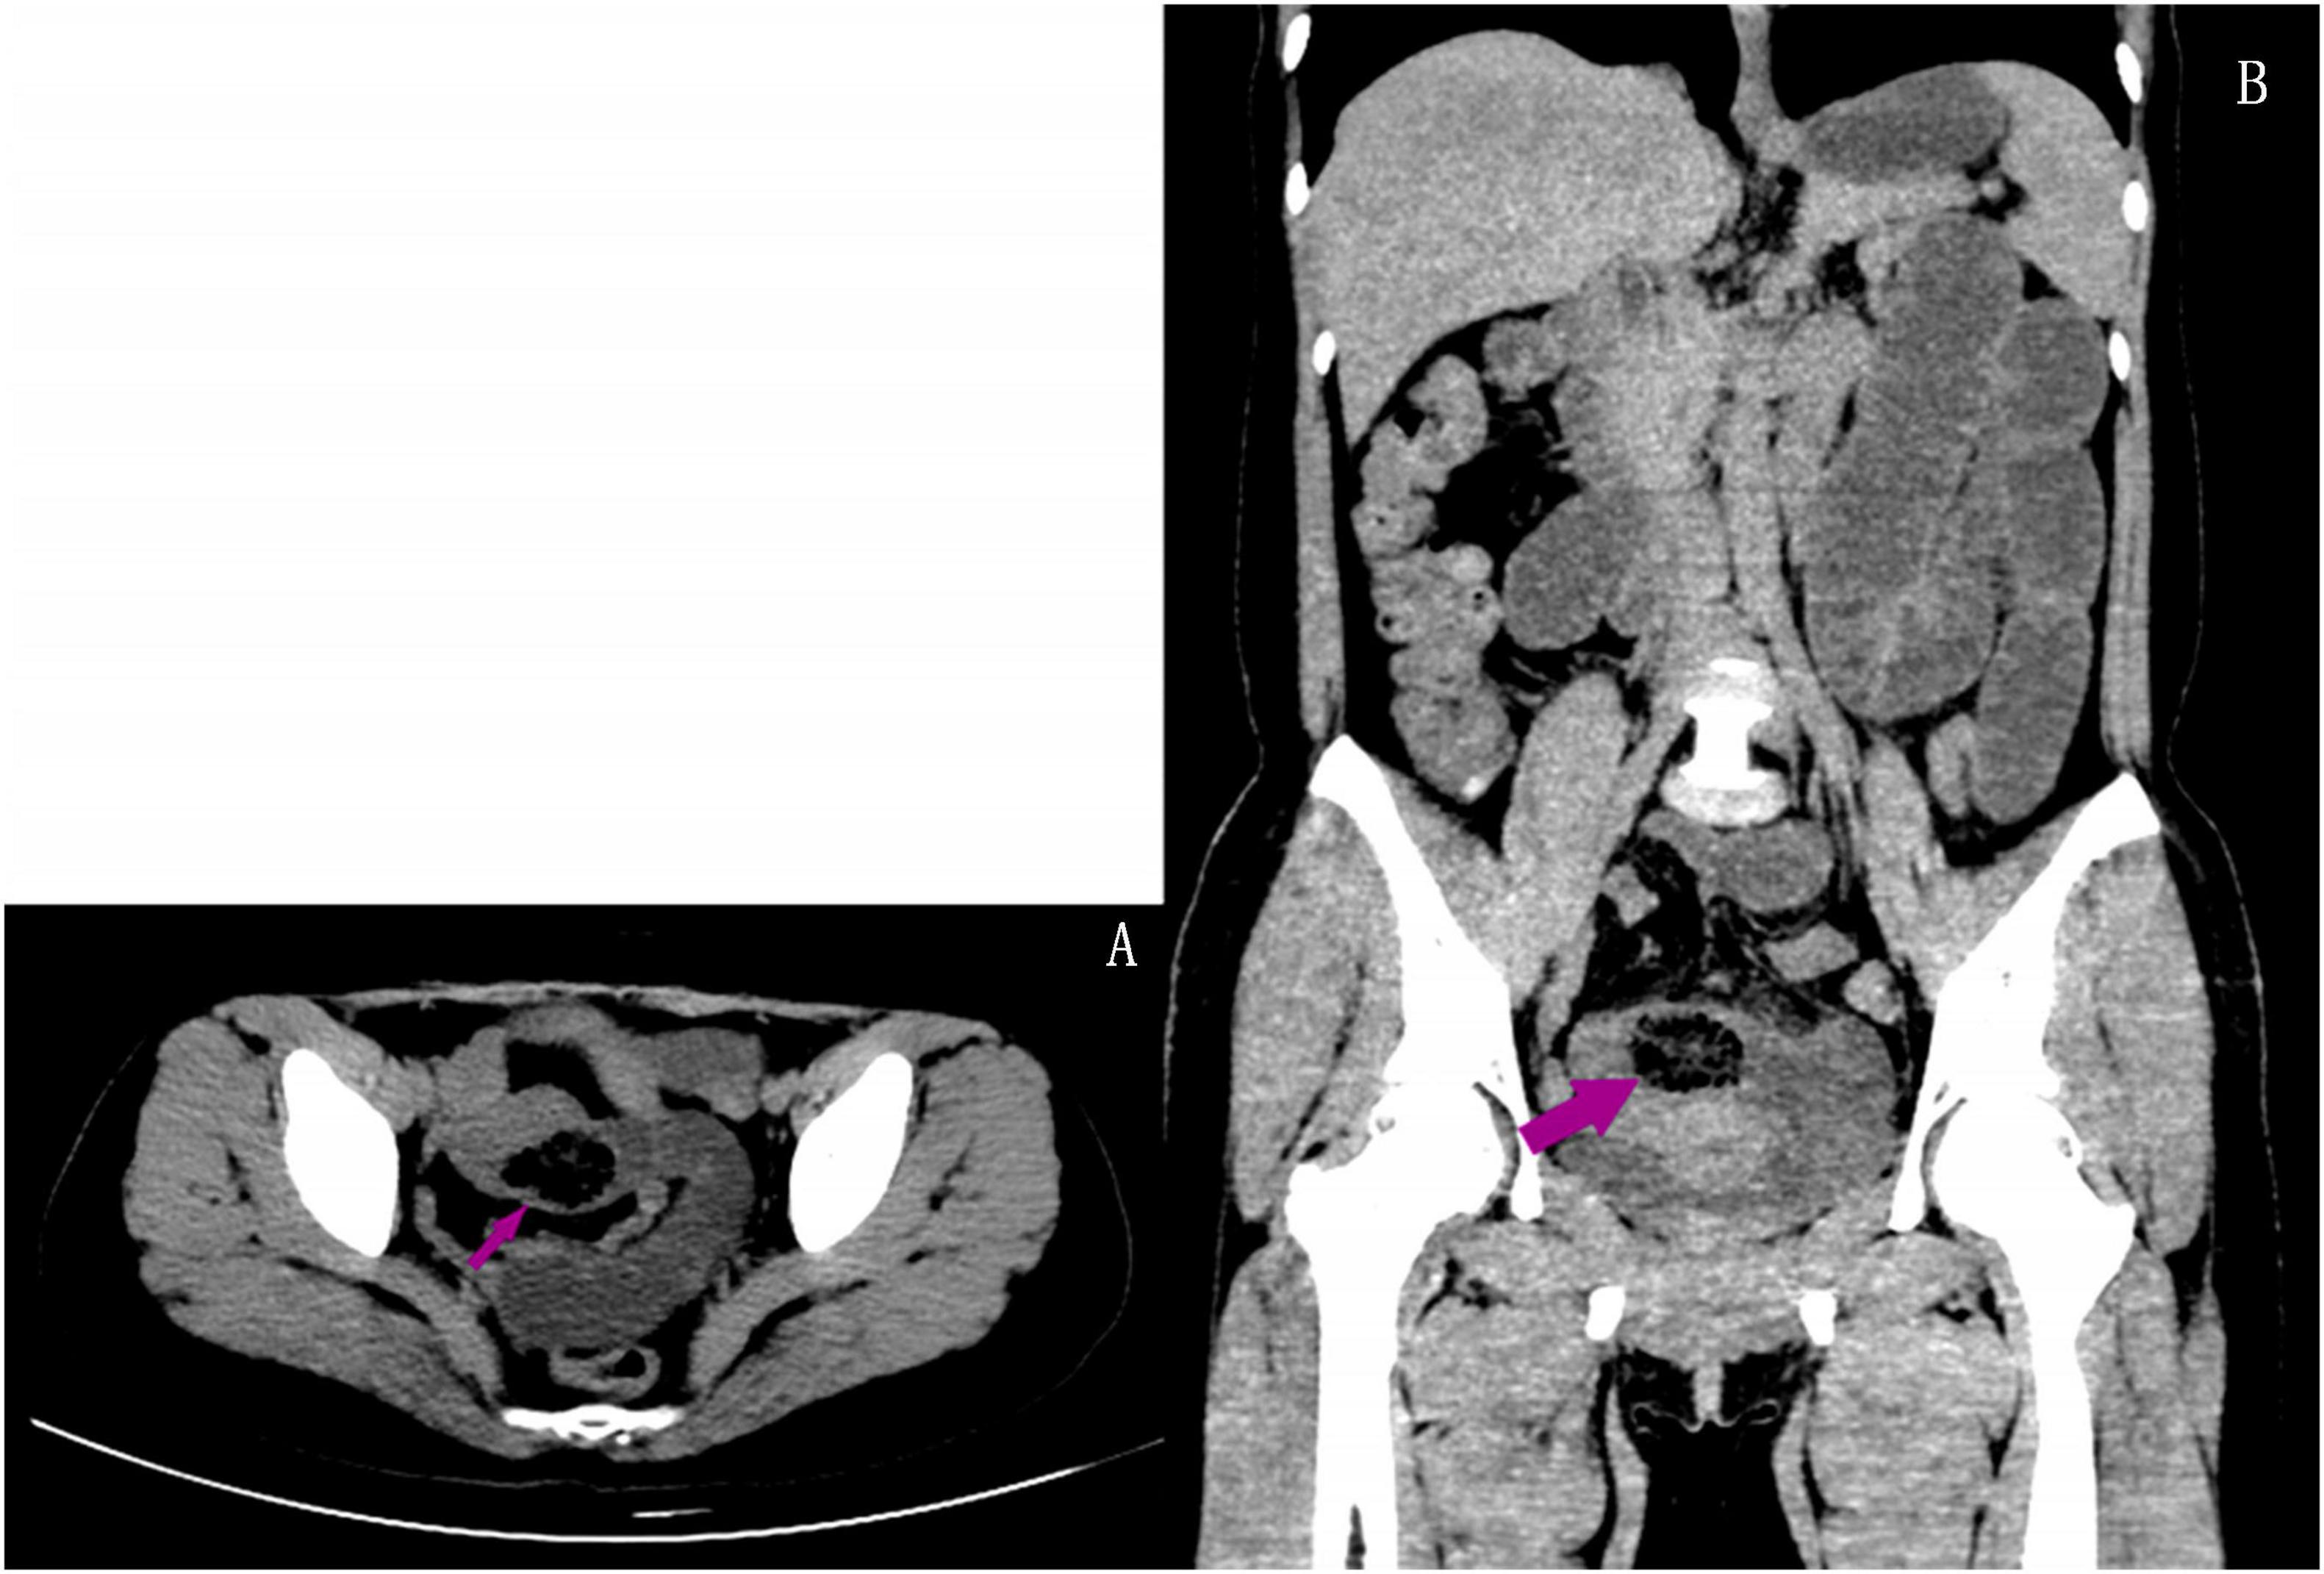

A 45-year-old female patient presented to the emergency department with a 5-day history of abdominal pain, nausea, and vomiting. The abdominal pain was colic-like, and abdominal distension was present; bowel movements and flatus were absent. The patient had a history of two cesarean sections and denied any previous GI issues. However, she reported the consumption of a large quantity of pears 2 days before the onset of symptoms. Physical examination revealed abdominal distension and tenderness upon palpation without rebound tenderness or muscular rigidity. Bowel sounds were diminished. Laboratory investigations revealed no significant abnormalities. A computed tomography (CT) scan showed several dilated small-bowel loops with fluid in the abdomen and a transition point in the right lower abdomen (Figure 1). The patient was diagnosed with SBO, and the possibility of a neoplasm was also considered. The patient was subsequently admitted for conservative management, which included fasting, intravenous fluid administration, antibiotics, and nasogastric tube decompression. Despite 28 h of conservative management, the patient’s symptoms persisted. Thus, we counseled the patient and the family in detail about the risks of continuing non-operative treatment—namely, bowel perforation, peritonitis, intestinal ischemia, surgical delay, symptom progression, and psychological stress while also explaining the potential risks and benefits of laparoscopic exploration. After careful consideration, the patient and family elected to proceed with laparoscopic surgery. No adhesions were observed during the surgical procedure, and a foreign body obstructing the intestinal canal was discovered approximately 60 cm from the ileocecal region. This obstruction resulted in significant dilation and fluid accumulation in the proximal intestinal canal, and the distal section collapsed (Figure 2). A 4-cm incision was made in the abdomen to access the obstruction site, and a longitudinal enterotomy was performed to extract the foreign body (Figure 3). The foreign body was identified as a bezoar measuring approximately 30 mm × 30 mm; the specimen fragmented into multiple pieces during extraction (Figure 4A). The bezoar was subsequently analyzed, revealing that it comprised undigested pear material (Figure 4B). The intestinal incisions were closed transversely, and the abdominal incisions were closed in a layered manner. The patient experienced an uneventful recovery and was discharged on the fifth postoperative day with dietary modification instructions to prevent future occurrences of gastrolithiasis. The patient showed no signs of recurrent SBO or surgery-related complications at the 3-month follow-up.

Figure 1. Axial (A) and coronal (B) abdominal CT scan revealing an oval mottled-appearing mass suggesting a bezoar (arrow), with proximal small bowel distension.